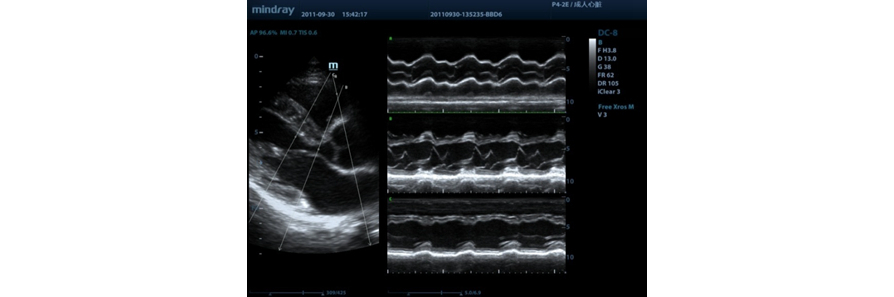

Free Xros M?

Modo M anat├│mico permite realizar las observaciones y medidas anat├│micamente precisas independientemente de la orientaci├│n. Provee mejores im├Īgenes a trav├®s de la visualizaci├│n simult├Īnea de hasta 3 l├Łneas M.